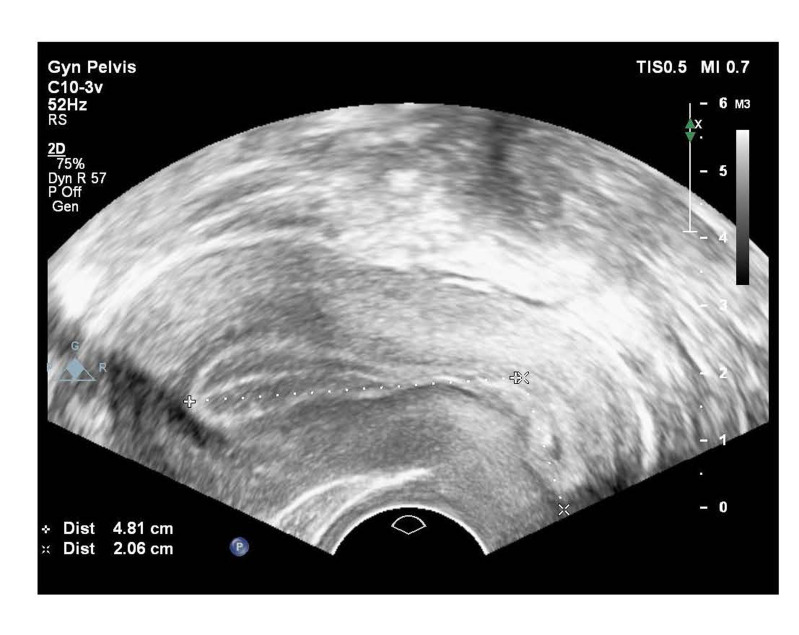

Background: Embryo transfer (ET) is an important step in assisted reproductive technology. Uterine length measurement before ET (ULMbET) enables the determination of catheter length and anatomical variation before the ET. Therefore, in this study, we aim to compare ULMbET and transabdominal ultrasound-guided ET (TAUGET).

Materials and methods: This open-label randomised clinical trial enrolled 264 women who were scheduled for frozen- thawed ET (FET) cycles. The women were randomised to the ULMbET or TAUGET group for ET. The primary outcome of this study was clinical pregnancy.